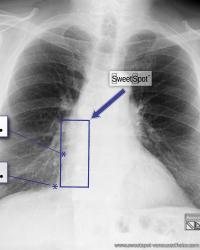

Figure - 19

How to draw the Sweet Spot™ |